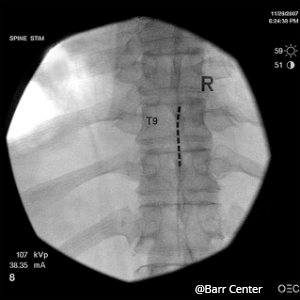

Before a permanent implantation can be performed, a trial implantation is performed to see if this device will be effective for your pain. This minor outpatient procedure is performed at our offices. It involves one or more leads (very thin wires) being placed in the epidural space. The leads contain electrodes that produce the electrical signals that result in stimulation. The leads are then connected to a small electronic device outside the skin worn on the back. This device will allow you to adjust the strength of the electrical impulse.

If this trial spinal cord stimulation is successful, you will then be referred for a permanent implantation in which new leads will be positioned and a small stimulator device will be implanted under your skin.